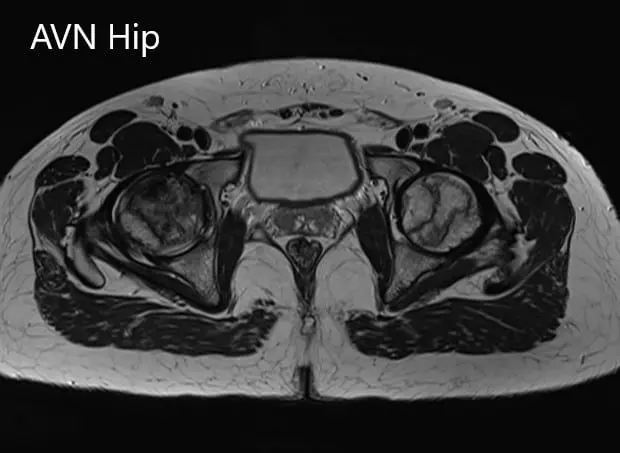

Axial sections of the T2WI and T1WI of MRI.

Hypointense areas were present on both T1WI and T2WI on both the head of the femur suggestive of sclerosis. Surrounding bone marrow edema was present and the bilateral necrotic area was approximately 70%.